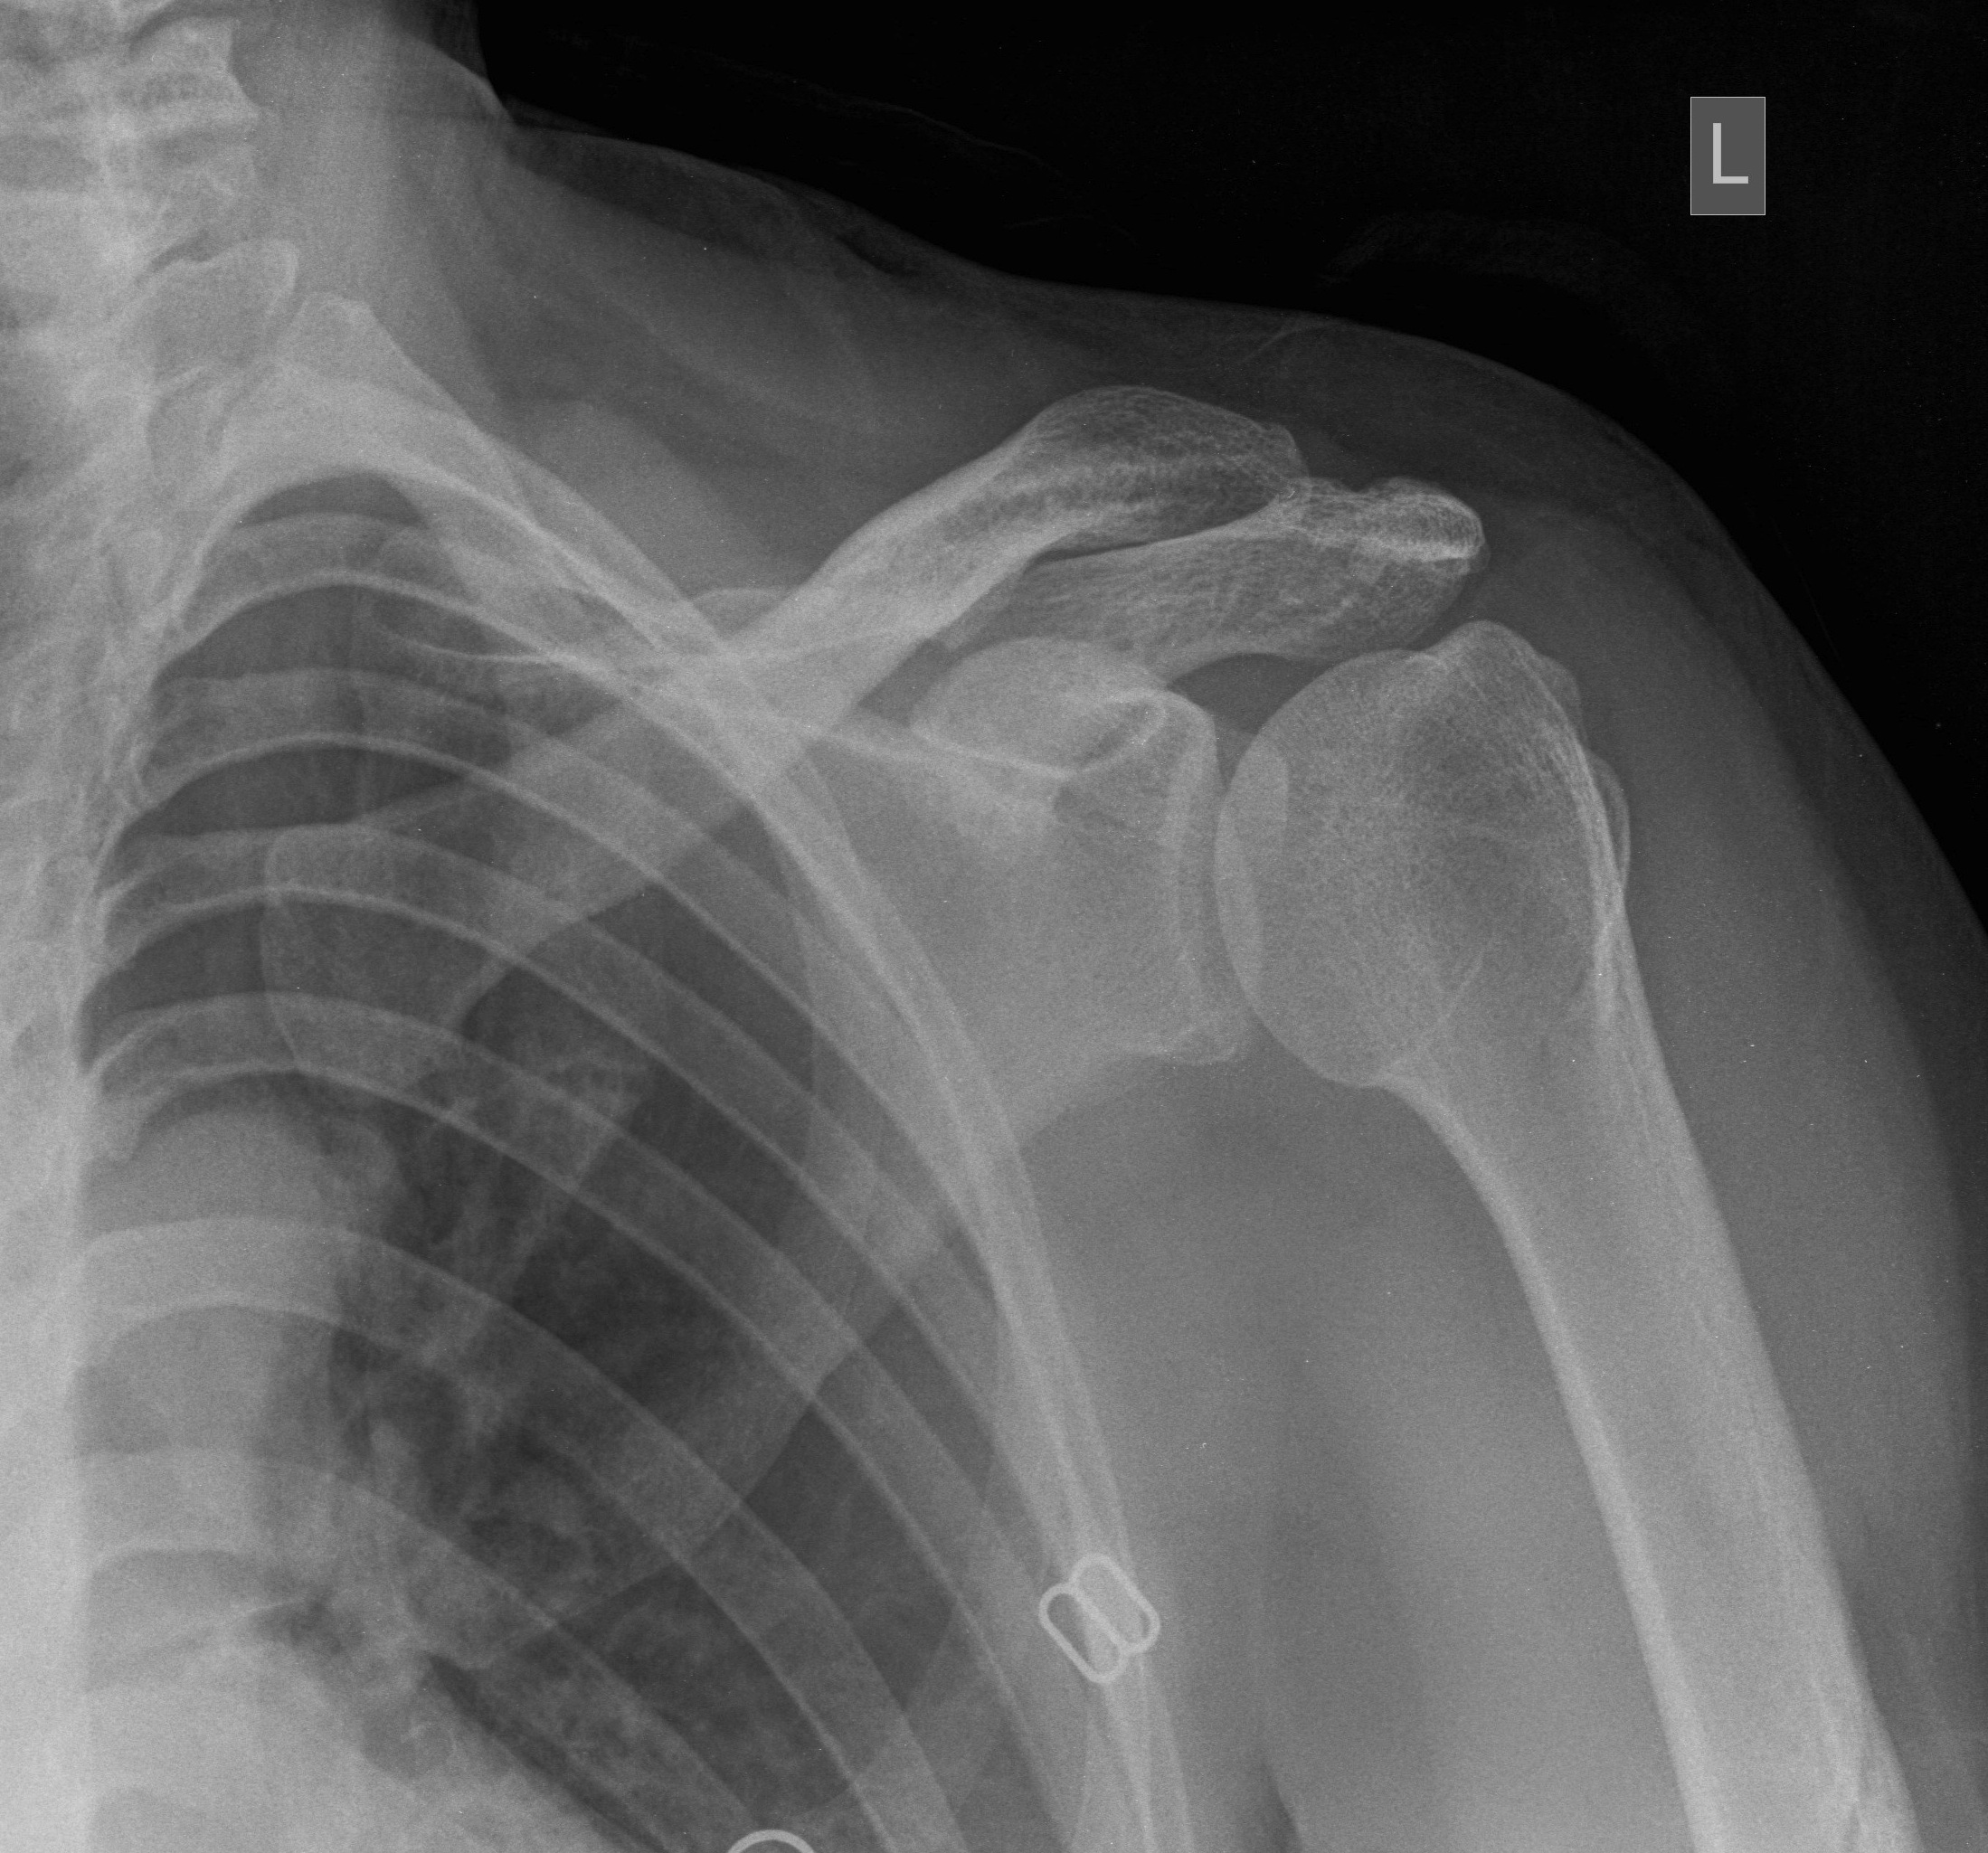

Рентген плеча: примеры снимков и их расшифровка